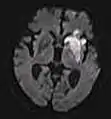

| Diffusion weighted (DWI) | Conventional | DWI | Measure of Brownian motion of water molecules.[66] | High signal within minutes of cerebral infarction (pictured).[67] | ![]() |